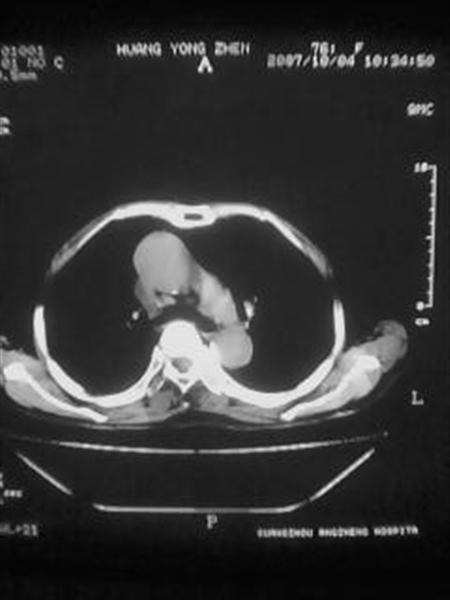

标题: CT10080:F76Y,各位老师发表高见!!! [打印本页]

标题: CT10080:F76Y,各位老师发表高见!!!

右下肺周围型肺癌伴双肺右侧叶间 胸膜及右肺门淋巴结转移

考虑:肺癌伴肺、胸膜 纵隔淋巴结转移可能性大!